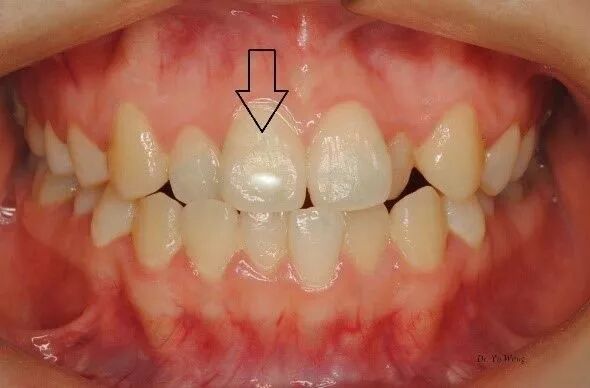

恒中切牙萌出后牙面即有白斑:此为釉质发育不全的一种,多出现在唇面。导致此问题的原因最可能出现在出生到一周岁时,如出生后较长时间的新生儿黄疸(高胆红素血症),或在围产期或出生后暴露于较高的双酚A环境,影响釉质沉积所致。如果侧切牙受影响,那么问题可能发生于1岁或更晚些时候。

中切牙面小白斑为釉质沉积受干扰所致